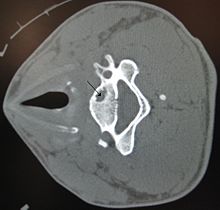

Géode osseuse dans la vertèbre cervicale.

Une géode (osseuse), en médecine, désigne une cavité d'origine pathologique, qui apparait dans les tissus d'un organe comme un os ou le poumon.

En radiographie, on peut repérer une géode par une image radiographique transparente :

- fond homogène ;

- contour tracé par une ligne continue ;

- cavité à contenu liquidien.